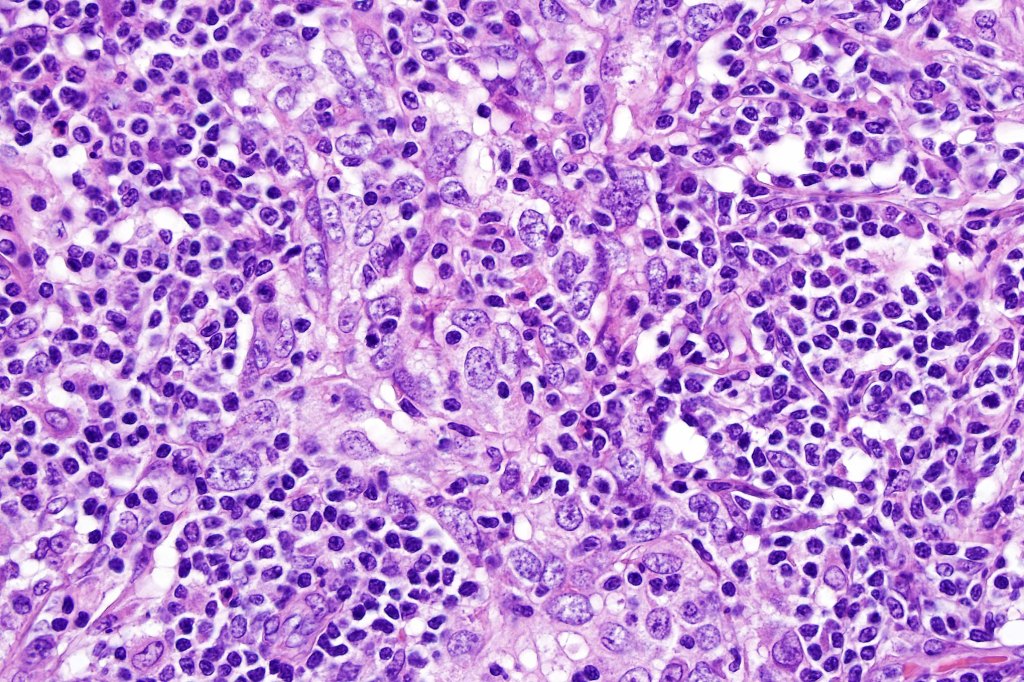

•Syncytial epithelial component in nests, cords or sheets surrounded by an intense lymphoplasmacytic infiltrate

•Epithelial cells are large with abundant cytoplasm and vesicular nuclei with conspicuous nucleoli

•Marked mitotic activity, variable pleomorphism

•Variable perineural infiltration